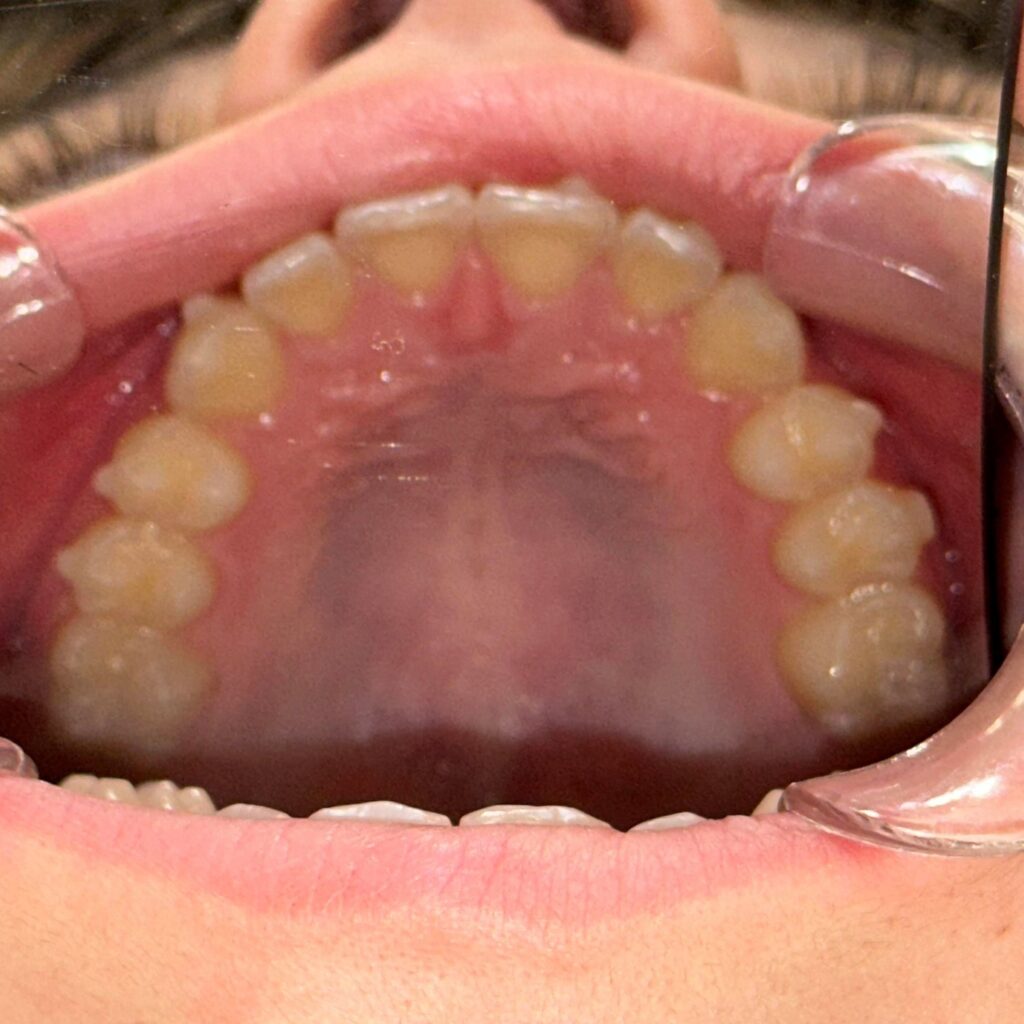

- wykonania precyzyjnego plan leczenia oraz indywidualnych skanów zębów Pacjenta skanerem wewnątrzustnym,

- umiejscowieniu na zębach przezroczystych zaczepów i nałożeniu pierwszego setu nakładek

Aparat Invisalign® w większości przypadków nadaje się dla każdego Pacjenta, który ma zęby wyleczone oraz wyczyszczone z kamienia i osadu.